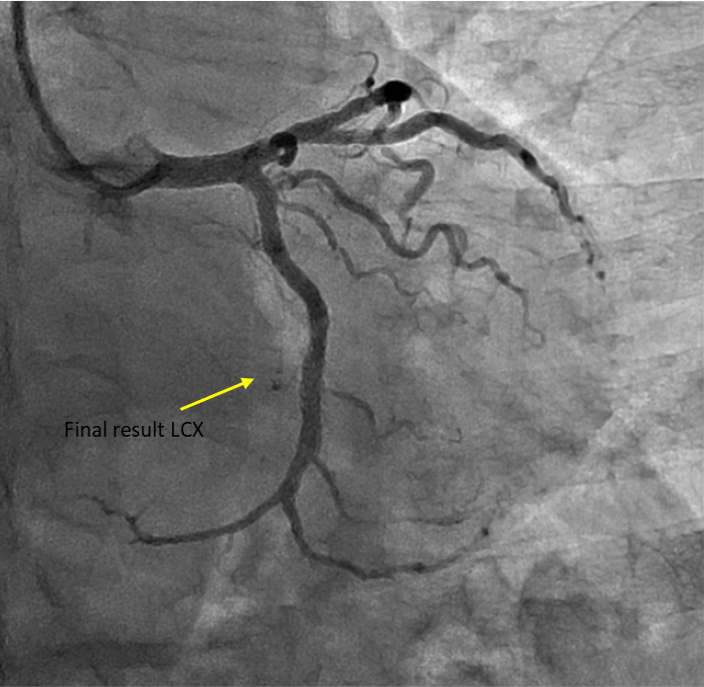

Percutaneous coronary intervention (PCI) was performed via transradial approach with 6 Fr radial sheath. Left coronary system was engaged using EBU 3.0 6 Fr guiding catheter. We decided for antegrade approach. Initial attempt with Fielder XT-A wire with a microcatheter support failed to cross the in-stent restenosis (ISR) lesion. We escalated to Asahi Gaia Second wire and successfully crossed the lesion to OM branch. Subsequently, wire was exchanged to a workhorse wire Runthrough Floppy via microcatheter. Lesion site was first predilated with a semi-compliant balloon Pantera Pro 2.0x 15 mm. Then, IVUS was passed down which showed previous stent site undersized, vessel size distal LCX of 4.0 mm. We further predilated lesion site with scoring balloon Scoreflex Trio 3.5x15 mm, up to 22 atm. Lesion site was acceptably prepared, then Paclitaxel drug-coated balloon Prevail 4.0x25 mm was deployed at nominal 6 atm for 60 seconds. Repeated IVUS run showed good stent apposition with MSA of 9.5mm2 proximally and 6.6mm2 distally. Final fluoroscopic shot showed good result with TIMI 3 flow, no stent edge dissection. Patient was symptom-free after procedure and discharged the following day.